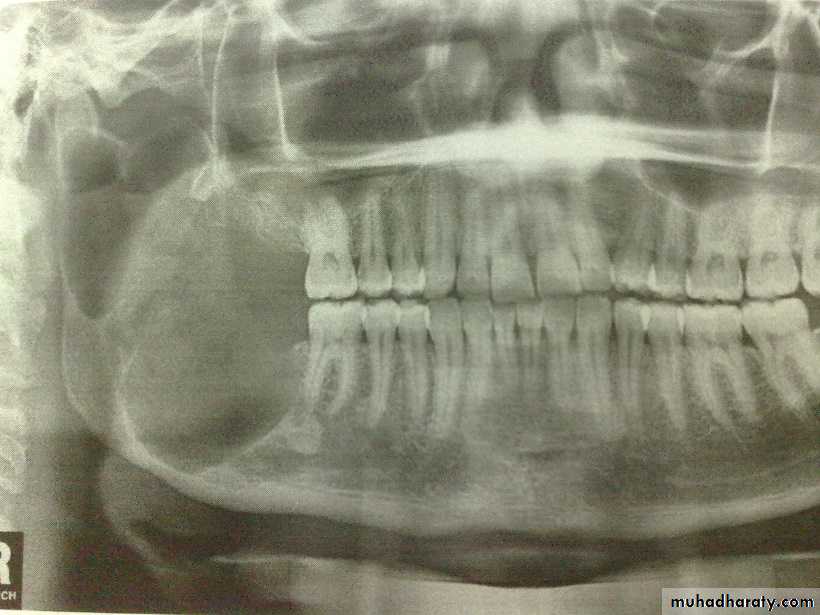

Raioraghical examination may demonstrate unlocular or multilocular types. Unilocular ameloblastomas may be confused with benign cysts. The tumors frequently absorbs the alveolus surrounding ,the roots of teeth and may absorb root ends.